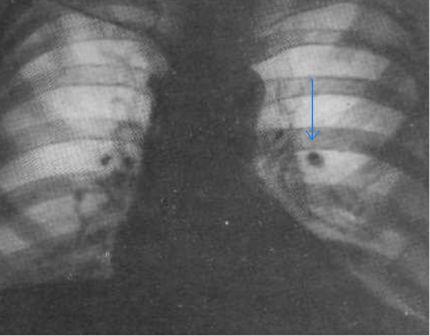

- ограниченные затемнения – интенсивная тень с четкими внешними границами. Встречаются при раках легких, пневмониях, ателектазах (спадение участка легкого) инородных телах, туберкулезе;

- неограниченные затемнения – тени на протяжении всей легочной ткани с одной или обеих сторон. Наблюдаются при крупозных пневмониях, грибковых заболеваниях, сердечно-сосудистых нарушениях, профессиональных болезнях;

- округлые затемнения – тени округлой формы больше 1 см в диаметре. Наблюдаются при раке легких, эхинококкозе;

- очаговоподобные – до 1 см в диаметре. Их формируют туберкулез, саркоидоз, силикоз;

- милиарная диссеминация – множественные мелкие тени на больших участках характеризуют туберкулез;

- тяжистость – интенсивные линии в легких наблюдаются при раке, саркоидозе, туберкулезе;

- кольцевидные тени с четким ободком и прозрачной внутренней частью – кисты и каверны в легочной ткани;

- просветления формируют на рентгенограмме заболевания с повышением воздушности легких – эмфизема, пневмоторакс, ателектаз.